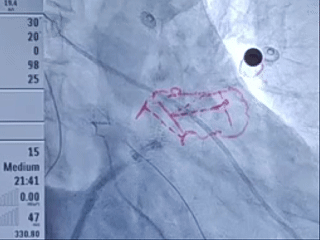

肝位输送LAFDQ-29封堵器

封堵器展开后造影

肝位

头位

牵拉试验后造影

牵拉稳定,且造影无残余分流。

测量压缩比

右肩位下测量压缩比为10.7%

封堵合适

造影后无残余分流